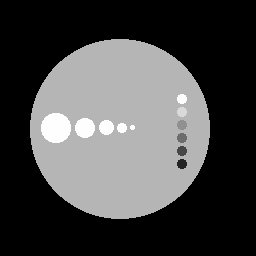

Images simulées : à gauche, haute résolution type IRM ou scanner X, à droite, base résolution type PET.

Après correction des effets de volume partiel par analyse multirésolution et fusion on obtient :

Le contour des disques est mieux délimité sans que l'information à l'intérieur ne soit dégradée. Ainsi les activités moyennes dans les 11 disques sont retrouvées avec une précision au moins aussi bonne que la méthode de référence* qui ne fait que de la correction quantitative sur des régions d'intérêt sans corriger les images proprement dites.